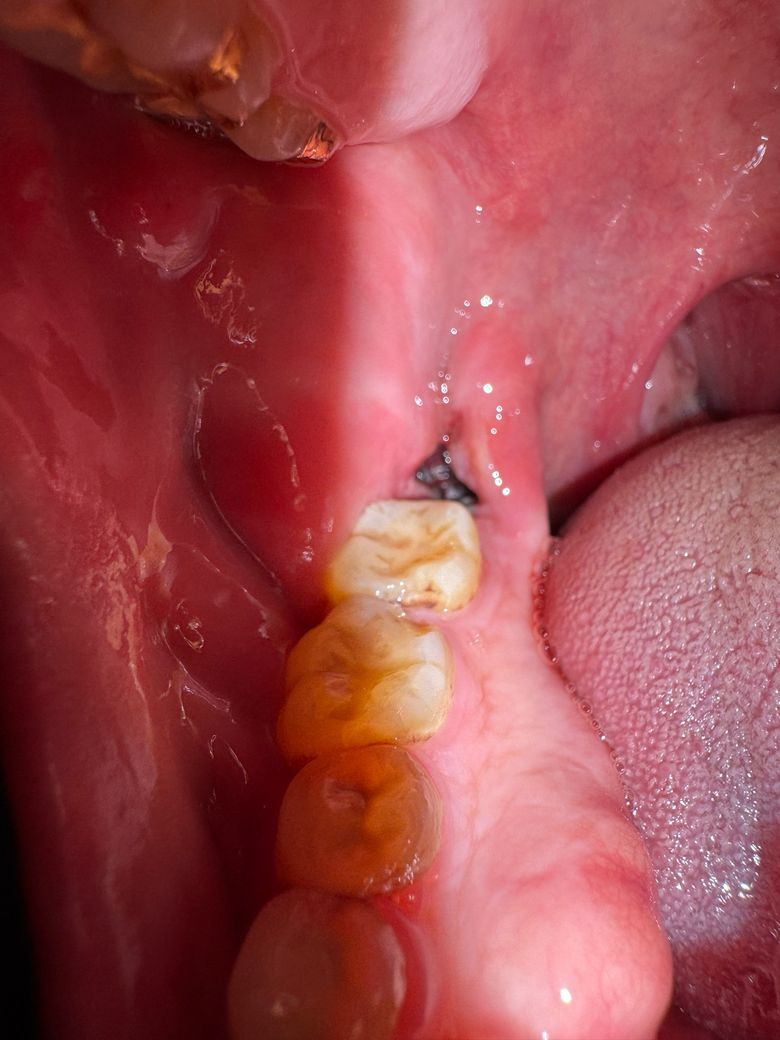

사랑니 발치 2일차, 지금 상태는 괜찮은건가요

음식물이 약간 끼어서 주사기로 가글액 분출해서 빼냈는데 약간 혈병이 씻겨나간건가 괜히 걱정되네요. 혈병이 굳어서 자리잡는건 언제부터인가요? 음식물을 섭취해야하는데 맘놓고 먹지도 못하겠어서요 불안해서…

사진상으로는 특별히 문제가 보이진 않습니다. 붓기는 조금 더 빠져야 하며 관리만 잘해주시면 됩니다.

지혈도 잘되고 발치한곳도 잘 아물고 잇는건 같습니다. 자극만 가지 않도록 해주시면될것같습니다.

혈병은 원래 발치 후 1~2일차에 다 흡수되어 잇몸치유에 필요한 조직이 됩니다 걱정마세요

사진으로 봤을 경우 사랑니를 발제한 부위에 혈병이 잘 유지되고 있으며 문제가 없는 것으로 보입니다. 해당 부위를 자극하지 않는 것이 좋습니다.